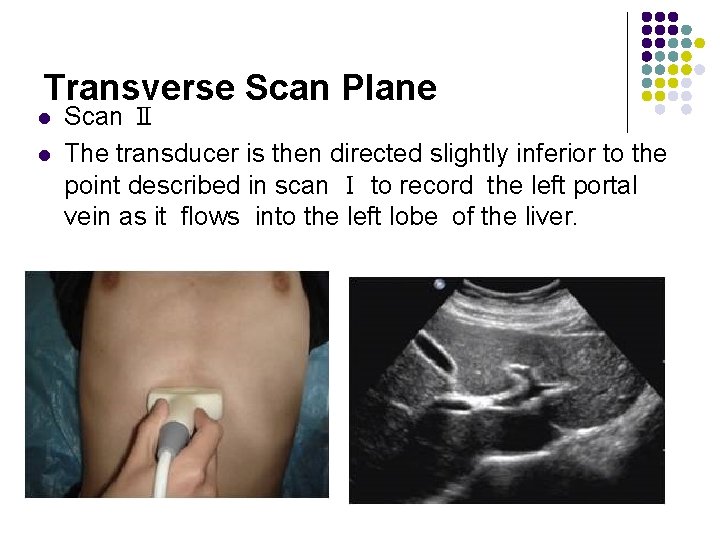

Transverse Scan Plane l l Scan Ⅱ The transducer is then directed slightly inferior to the point described in scan Ⅰ to record the left portal vein as it flows into the left lobe of the liver.